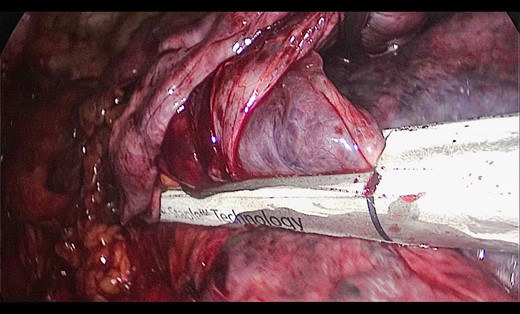

A 73-year-old male patient with a clinical history of COPD, lung emphysema and a 30-year smoking history was admitted to the ED due to a 24-h clinical picture of dyspnea immediately following a sudden bout of dry coughing. Physical examination showed a dyspneic patient, tachypnea of 25 rpm, heart rate of 85 bpm and blood Pressure of 135/75 mmHg along with central cyanosis. Chest exam showed a hyper-resonant right hemithorax along with reduced breath sounds. Initial chest X-ray revealed a large right-sided pneumothorax (Fig. 1). A right chest tube was placed in the ED. Emergency echocardiogram had no significant findings and spirometry showed suspected patterns of obstruction. Following patient stabilization, a high-resolution chest computed tomography (HRCT) was performed revealing extensive pan lobar emphysema throughout both lungs, para septal emphysema in both the anterior upper lobes and herniation of a left lung bullae through the anterior mediastinal pleura along with a right-sided pneumothorax with the chest tube in place with persistent air space (Fig. 2). The patient was taken to surgery where a right video-assisted thoracoscopic (VATS) approach showed severe lung emphysema and a contralateral herniated left lung bulla through the mediastinal pleura anterior to the pericardium (Fig. 3). Right pleurodesis was performed using Talc and a left posterior thoracoscopy showed a severe emphysematous left lung with a lingular herniated bulla to the right hemithorax through an anterior mediastinal pleural defect along with pleural adhesions (Figs 4 and 5). Thoracoscopic hernia reduction was performed along with bullectomy using 60 mm mechanical sutures (Fig. 6). Chest tubes were removed on POD 3 (right) and POD 4 (left). The patient had significant respiratory improvement and was discharged on POD 5.

Thoracoscopic view from left side of transmediasinal hernia of pulmonary bulla after reduction (asterisk).